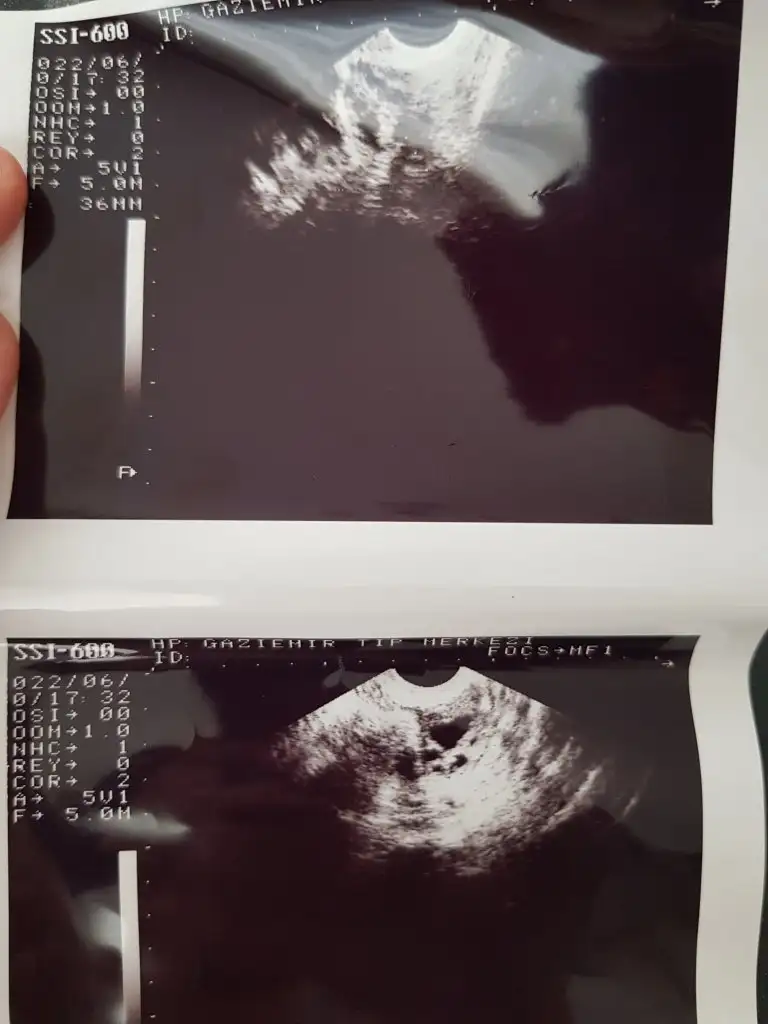

Merhaba eşimle hamileik için bu ay denemeler yaptık bir kez de değil hani yumurtlamadan önce sonra yumurtlama zamanı falan baya denedik yani olur diye düşünmüştüm açıkçası hattâ birkaç belirti de vardı fakat tüm testlerim hep negatif cikti kan vermistim oda negatif çıktı 1.20 çıkmıştı 2 gjn once kanama oldu leke şeklinde siyahımsı kahverengimsi değişik yerlesme kanaması sandım çünkü adetime 5 gün vardı ertesi gün bi baktım baya akışkan olmuştu ki karnım da ağrımaya başlamıştı kasiklarim falan bugün 3. Gün az önce doktordan geldim kistten falan şüphelendim çünkü seneler önce bir doktor bana cikolata kistjn var demisti sknra baska bir doktora gitmistim yok dedi bol su ic demisti o gunden beri gitmedim taki evlendim simdiee cocyk istoyiruz ilk defa bu ay denedik bu ayi ful degerlendirdik fakat 5 gun erken kanama basladi regl oldum bugjn 3. Günüm doktora gitmek istedim gittik kist icin doktor yok dedi fakat rahmin 12 m dedi normalde çok ince olması gerek dedi bu kanama adet kanaması değil dedi başka dedi hamilelik falam olabilirmi dedim olabilir dedi fakat adetim şuan bildiğiniz hala kanama var ve bu bende normal adetten farklı olarak bir kanama ilk başlarda ağrısız olmuştu su gibiydi akışkan pihtisizdi 3-4 aydir böyle arada pıhtı oluyor bende regl oluyorum saniyordum ama baska bisey varmis galiba bence rahim kalinlasmasi bu aya ozel bisey degil gibi acaba hamile kaldim sonra icimde olmadi falanmi ya kafamda bir sürü şey var baya taktım adet kanaması değil dedi özele gitmiştik kan testi istedi oda fiyat baya yüksek gelince devlete gidelim dedik bakalım tekrar doktora gidicem korkuyorum inşAllah kötü bisey yoktur böyle bi durum yaşayan varmı yada bilgisi olan acil yardımcı olurmusunuz lütfen kendimi hiç iyi hissetmiyorum inşallah bilgisi olan vardır şimdiden çok sagolun  buarada ikili fotoğraf yumurtalıklarımın onlar iyi dedi doktor tekli olan fotoğraf rahmimin onada kalınlaşma var dedi fakat ben fotoğrafta yuvarlak bisey görüyorum ne olabilir acaba ?Yarın adet günüm umarım olmam yazarım hamile kaldiysam o ara kanamanın olması büyük şans dedi doktor hemen değerlendirin dedi yaptık bakalım inşallah